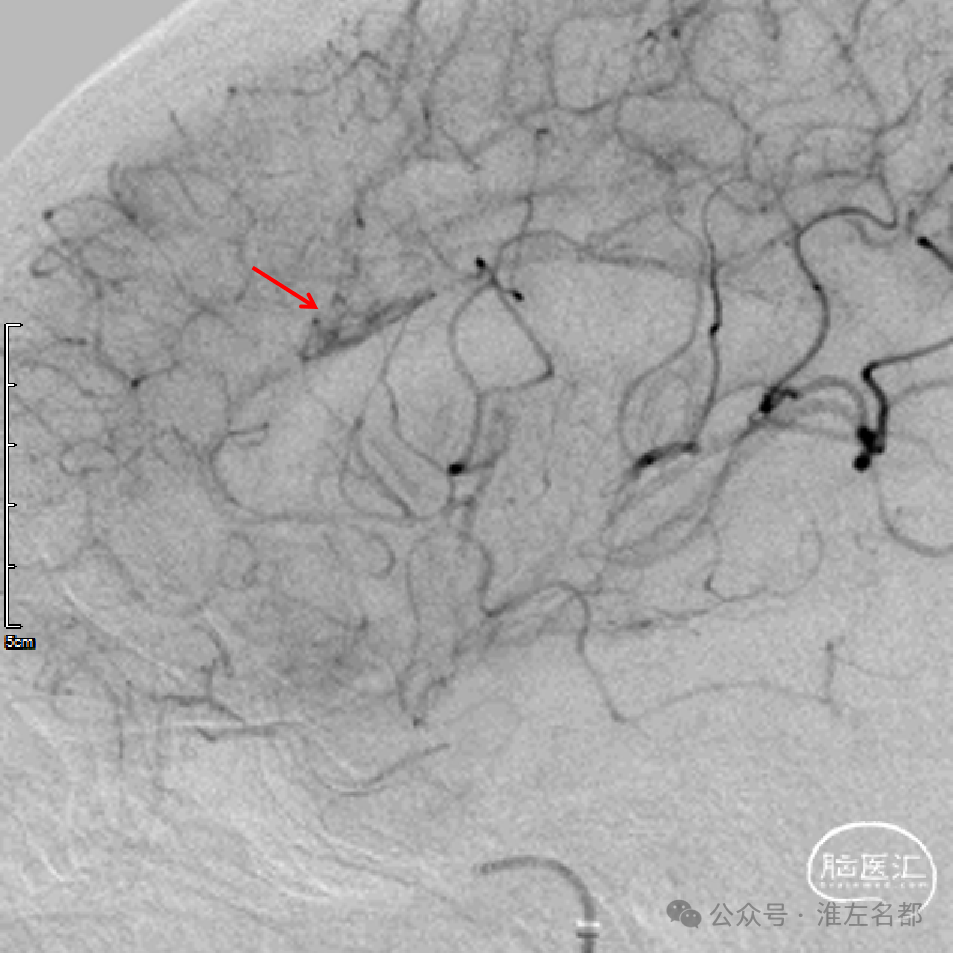

回收取栓支架后造影:闭塞再通,右侧A2局部轻微狭窄,但A3-4交界处可见造影剂渗出,提示出血。

予以降压等处理,约5分钟后造影提示出血已经停止。

术中DSA平板CT示:前纵裂旁少量蛛网膜下腔出血。